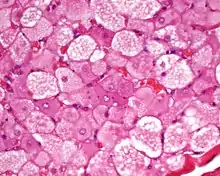

| Micrograph of a hibernoma. H&E stain. | |

The tumors histologically resemble brown fat. There are four histologic types recognized, but one is the most frequently seen (typical). There is a background of rich vascularity.

- Lobular type: Variable degrees of differentiation of uniform, round to oval cells with granular eosinophilic cells with prominent borders, alternating with coarsely multivacuolated fat cells (pale cells). There are usually small centrally placed nuclei without pleomorphism. The cells have large cytoplasmic lipid droplets interspersed throughout.[3][4]

- Myxoid variant: Loose, basophilic matrix, with thick fibrous septa, and foamy histiocytes

- Lipoma-like variant: Univacuolated lipocytes, with only isolated hibernoma cells

- Spindle cell variant: Spindle cell lipoma combined with hibernoma